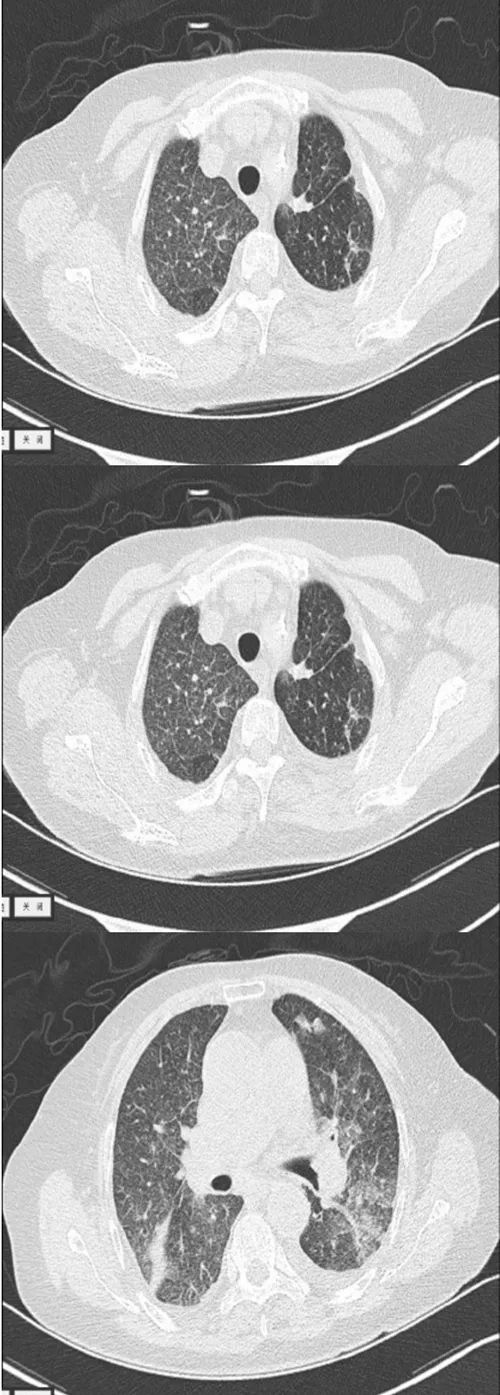

查血常规+CRP+PCT:WBC 2.10×109/L、N 90.4%、CRP 85.75mg/L、PCT 0.28ng/ml;肺部CT:两肺广泛感染,两肺广泛小粟粒状结节,两侧胸膜增厚(图1)。3次痰找抗酸杆菌均阴性,先后予头孢曲松针、头孢哌酮舒巴坦针、美罗培南针抗感染治疗效果不佳。

图1 患者的肺部CT表现